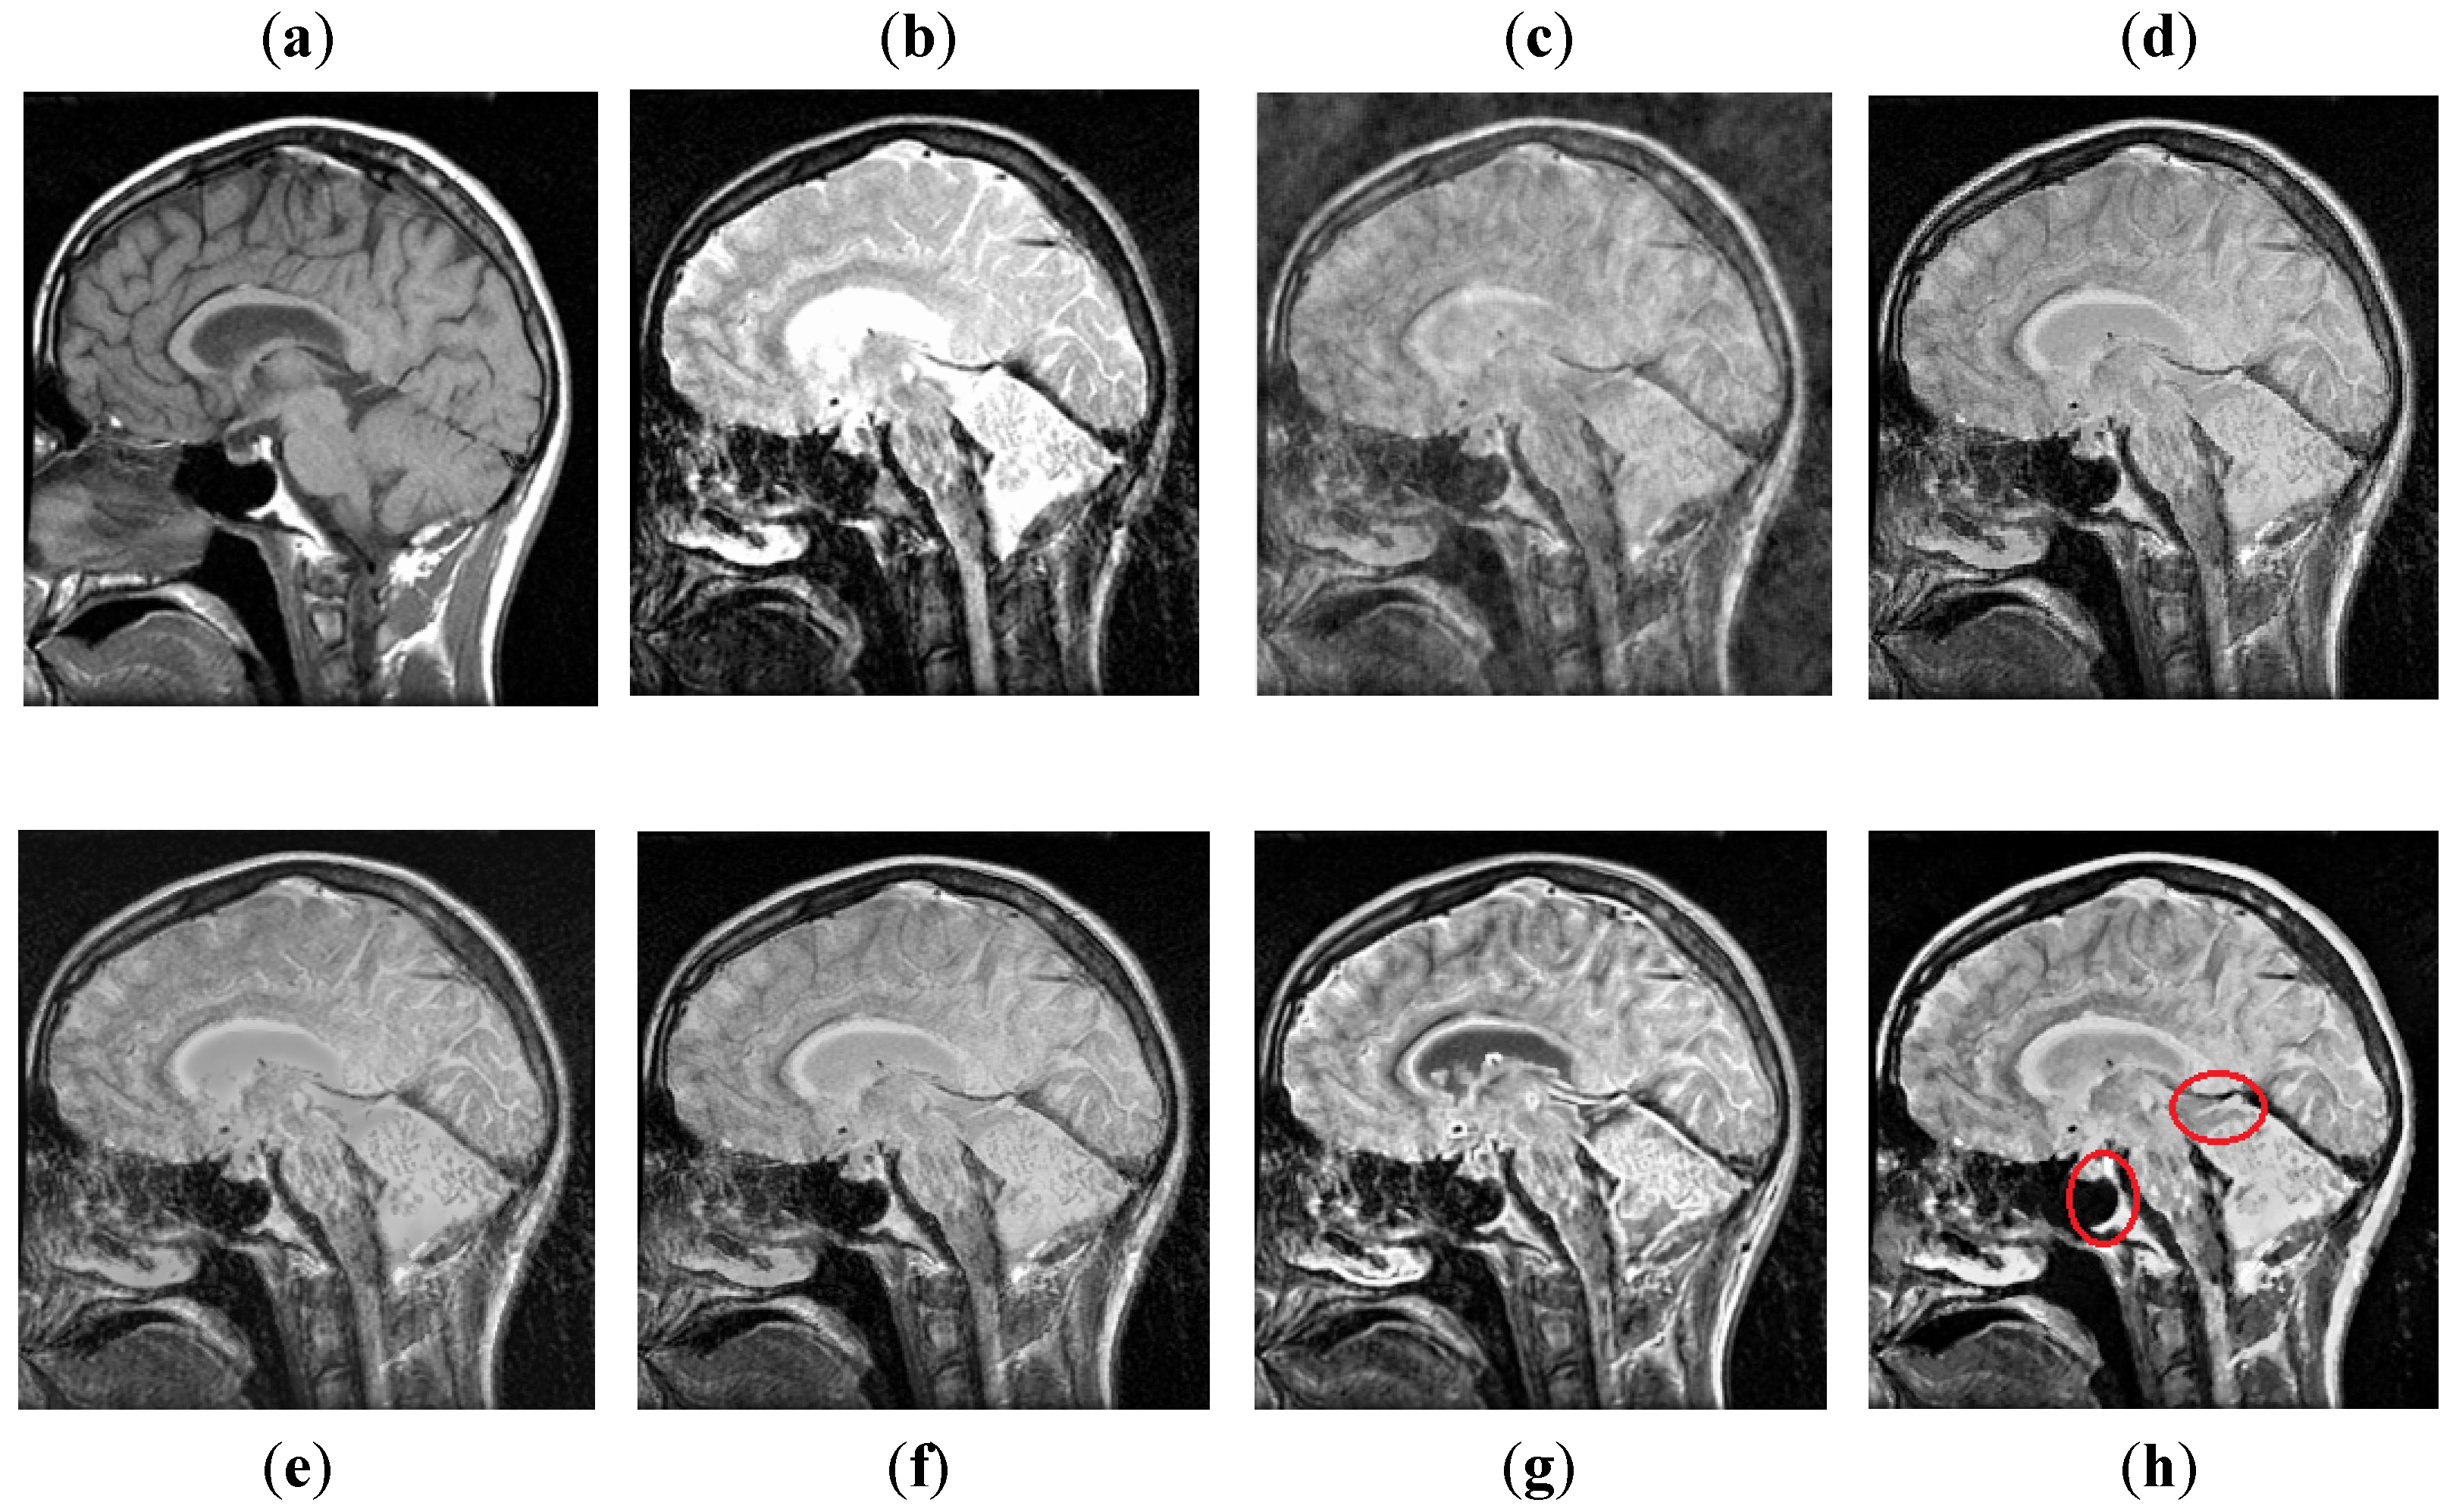

It can be observed in Figure 7 that images obtained by DCT have more noise and artifacts that distort the quality of a final image. The DWT method produces less noise than DCT, but the overall image is blurred, which affects the quality of the image. The NSST-SF-PCNN and CSR have better visual effects and produce better quality, but the image is still blurred, and some information is lost. The CNN method produces better results, and the image is more vivid and smooth than other existing methods, but its contrast and sharpness of the edges are still not up to the mark. It can be analyzed that the proposed method acquires better results than all mentioned fusion methods. The fused image has very negligible noise with better contrast. The edges are sharper with smoother boundaries. Hence, the final image has better visual effects with more salient information.

Figure 7. Data-1: (a) CT image, (b) MRI image, (c) DCT, (d) DWT, (e) NSST-SFT-PCNN, (f) CSR, (g) CNN, and (h) Proposed.